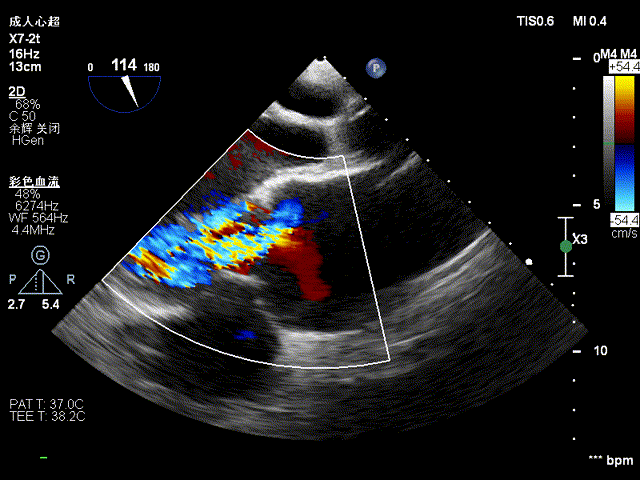

心超显示:二尖瓣位见生物瓣架回声,瓣叶增厚、回声增强,收缩期可见瓣叶脱向左房侧,闭合错位,瓣环径约1.9cm;三尖瓣形态、开放可,闭合欠佳;主动脉瓣形态、开放可,闭合欠佳。二尖瓣口收缩期左房侧见大量反流信号,二尖瓣口反流VC约0.6cm;三尖瓣口收缩期右房侧见少量反流信号;主动脉瓣口舒张期见少量反流信号;

术前食道超声提示二尖瓣生物瓣大量反流:

即刻行食道超声显示无瓣周漏: